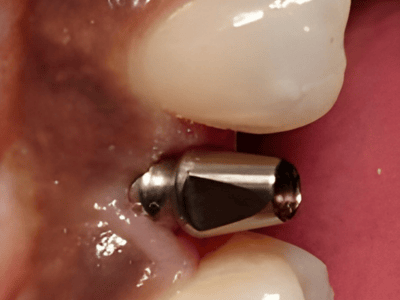

Dr. Deeksha Bhardwaj is a highly skilled dental specialist in Greater Noida, specializing in

Periodontics, Dental Implants, and Advanced Gum Care. With a BDS and MDS in Periodontics, she

provides expert treatment for gum diseases, receding gums, and dental implant procedures using the

latest technology.

Dr. Bhardwaj holds a BDS and MDS in Periodontics, specializing in gum health, dental implants, and advanced periodontal care.

Dr. Bhardwaj specializes in Periodontics, offering treatments for gum diseases, dental implants, laser dentistry, root canal treatments (RCT), teeth whitening, smile makeovers, and general dental care.